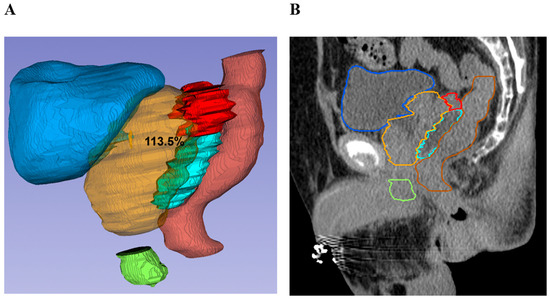

Prostate–Rectum Spacing from Apex to Base and Its Impact on Organs-At-Risk Dosimetry in Prostate Cancer SBRT

Stereotactic body radiation therapy (SBRT) for localized prostate cancer delivers high doses per fraction, making dose constraints for the rectum and other organs at risk critical during treatment planning. This study evaluated the association between prostate–rectum separation, achieved with a biodegradable balloon rectal spacer at different anatomical levels, and corresponding organ-at-risk dose patterns. Thirty-three patients underwent transperineal balloon spacer implantation followed by SBRT to 36.25 Gy in five fractions. Prostate–rectum separation at the apex, mid-gland, and base were measured on CT and/or MRI and categorized as <10 mm, 10–14 mm, or ≥14 mm. Rectal dose–volume parameters and mean doses to the rectum, bladder, and penile bulb were assessed using linear regression analyses and group comparisons at 14 mm separation. Mean prostate–rectum separation was 16.6 mm overall, with minimal high-dose rectal exposure observed. Increasing separation was associated with reduced rectal dose–volume parameters at the apex and mid-gland, while greater base separation corresponded primarily to lower bladder mean dose. Increased apical separation was also associated with reduced penile bulb mean dose. No acute gastrointestinal toxicity was observed, and genitourinary toxicity was limited to low-grade events. These findings indicate that prostate–rectum separation varies by anatomical level and is associated with distinct organ-at-risk dose relationships in prostate SBRT. Full article

Figure 1